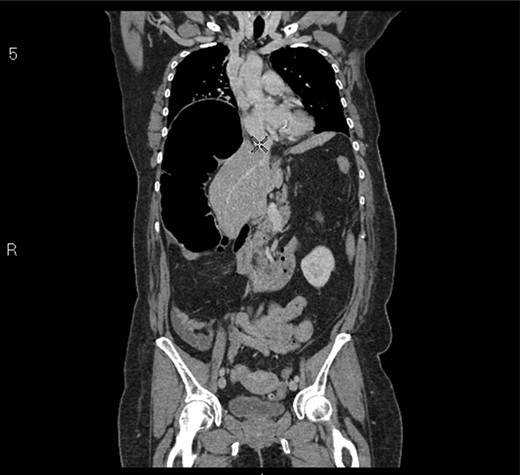

A 58-year-old female with a past medical history of a large intrathoracic hiatus hernia presented to her general practitioner and was subsequently referred to our surgical department with symptoms of sudden onset severe epigastric pain associated with vomiting and abdominal distension. Her abdomen was generally tender, maximally in the epigastric region, although she was not peritonitic. The admission erect chest radiograph showed a large hiatus hernia and an elevated right hemidiaphragm with a large loop of distended bowel (Fig. 1). Subsequent computed tomography (CT) scan demonstrated an almost completely intrathoracic stomach with a degree of volvulus, and the liver medially displaced by a loop of large bowel felt to be caecum (Fig. 2). Since the patient remained otherwise well, bidirectional endoscopy was performed, and given that a volvulus point could not be identified and the ileocaecal junction was not identified, contrast studies were requested (Figs 3–5) which demonstrated an incomplete obstruction caused by a volved caecum rotated anteriorly and cephalad.

CT coronal section demonstrating caecum medially displacing the liver and causing an upward pressure on the right hemidiaphragm.